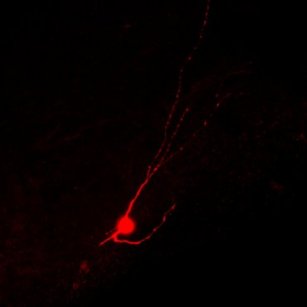

Mature inhibitory neuron derived from human embryonic stem cells is shown after successfully migrated and integrated into the injured mouse spinal cord.

Photo by Jiadong Chen, UCSF

It turns out that the bladder control loss and chronic pain may be due to overactive nerve signals. So the lab of Arnold Kriegstein transplanted inhibitory nerve cells – derived from human embryonic stem cells – into mice with spinal cord injuries. The scientists observed that these human inhibitory nerve cells, or interneurons, successfully made working connections in the damaged mouse spinal cords. The rewiring introduced by these interneurons also led to reduced pain behaviors in the mice as well as improvements in bladder control.